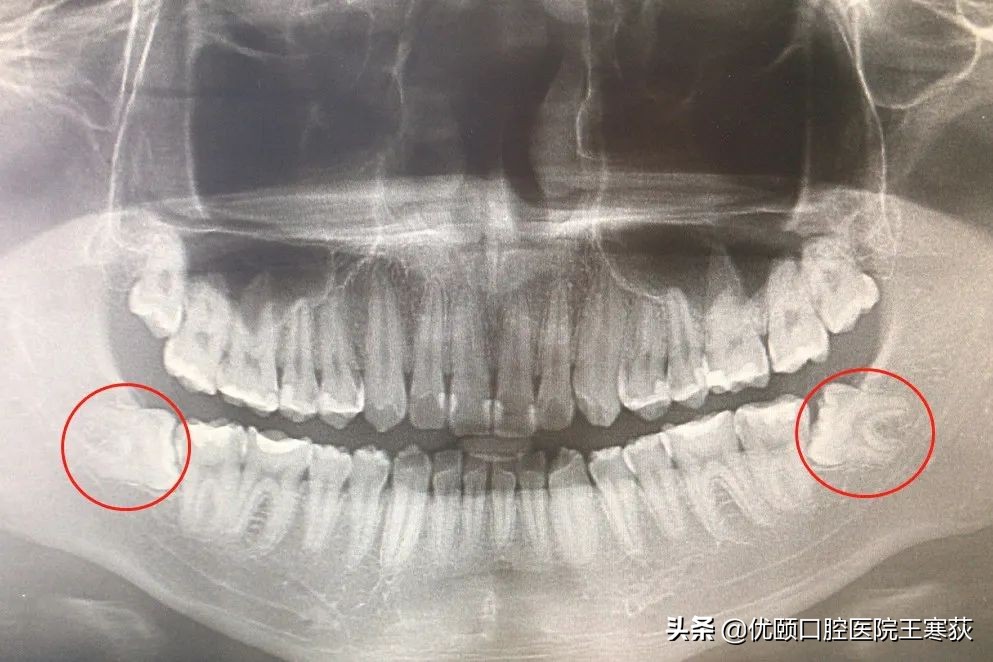

然而最近一次就2020年初,复查的时候发现了有几个补的牙,材料都还好好的,但是牙边缘已经继发龋了,而且还有两颗水平阻生智齿对前牙有影响,所以就建议他拔除。州州一听到拔牙就更害怕了,首先就想到了出血呀、切开呀、缝合呀,但是不拔以后就会有危害。经过几天的纠结,还是下定决心,拔掉那两颗智齿,但是州州确实非常害怕,所以呢崔医生就建议他使用舒眠治疗。 舒眠治疗就是在深度睡眠的情况下进行牙齿治疗,整个过程不知道也没有记忆 。州州觉得这个治疗方式很好,既能很好地配合医生,又能在睡觉的过程中把牙齿问题解决,非常愿意选择这种方式。

继发龋嵌体修复&水平阻生齿拔除